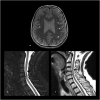

Findings: We describe a case of a 68-year-old woman with slowly progressive ataxia with paresthesia. Laboratory tests were normal. Total spine MRI showed a C4 posterior spinal cord lesion. Lumbar puncture was positive for oligoclonal bands with normal IgG index and protein level. Paraneoplastic antibodies were not detected. Electromyography showed nonlength dependent sensory neuropathy. The patient was treated with intravenous immunoglobulin for suspected dysimmune myelitis. Over 6 years, she progressively developed other neurological manifestations evoking CANVAS. Nerve conduction study showed isolated sensory impairment over the years and peripheral nerve ultrasound revealed abnormally small nerves. Further genetic testing confirmed the diagnosis.